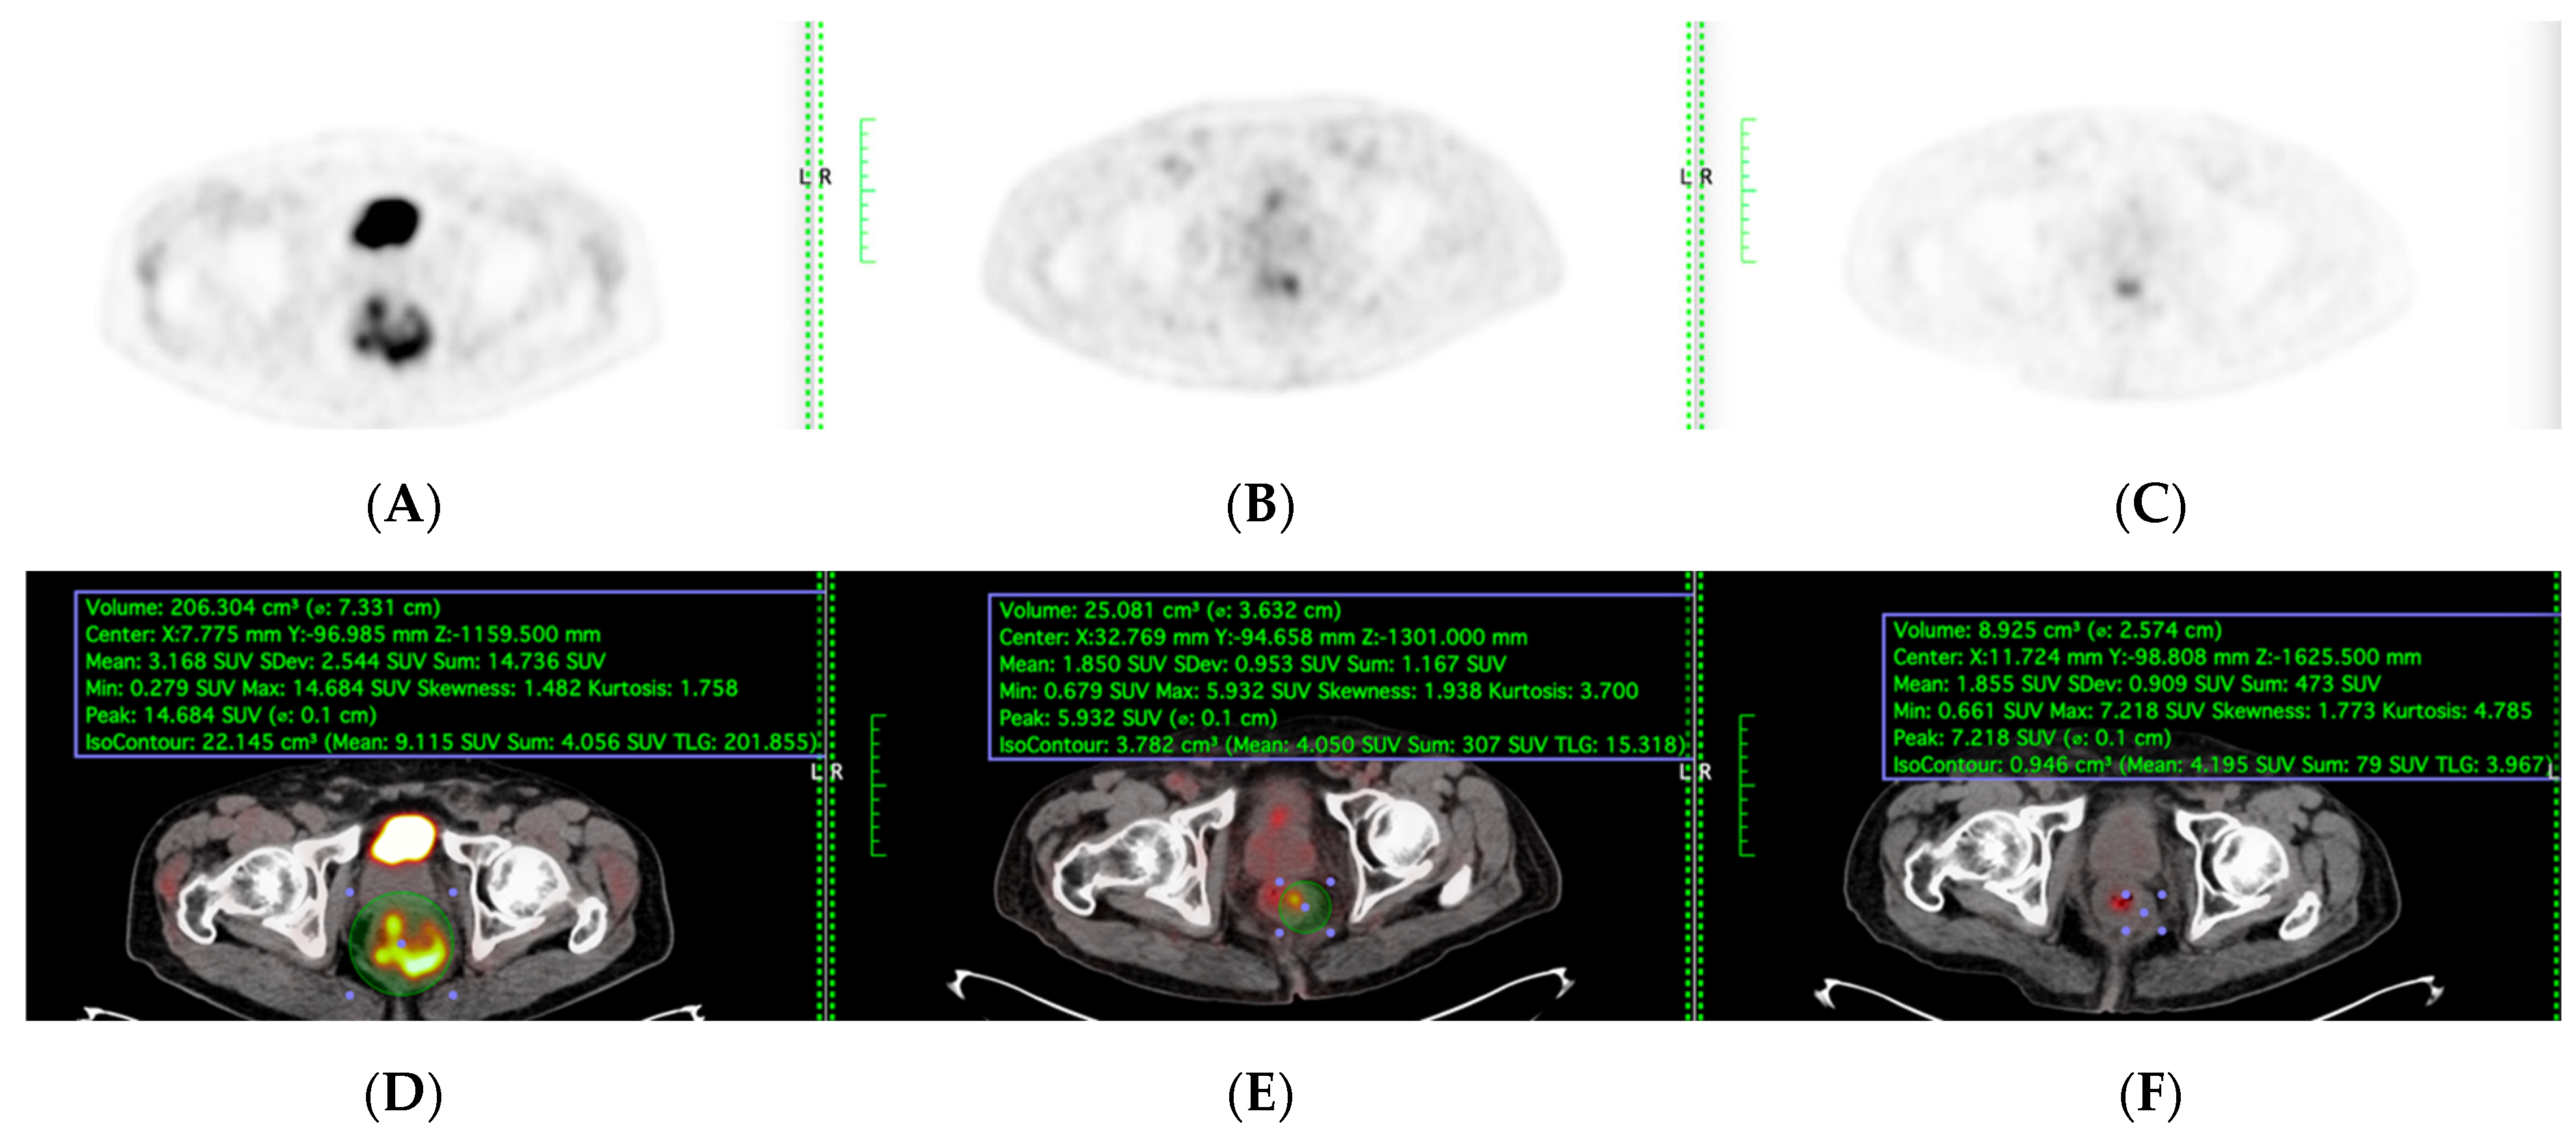

PET-CT, including maximum standardised uptake value (SUVmax) and total lesion glycolysis (TLG), were evaluated among the patients who underwent sequential PET-CT before, during, and after TNT were included (Figure 2). Total Lesion Glycolysis (TLG) was automatically calculated using vendor-specific software by multiplying the metabolic tumour volume (MTV) by the mean standardised uptake value (SUVmean) within the volume of interest (VOI). Lesion boundaries were delineated using a fixed SUV threshold of 2.5 with manual adjustment to exclude physiologic bowel uptake and adjacent organs, consistent with PERCIST guidelines. Sensitivity, specificity, accuracy, and areas under the model’s receiver operating characteristic curve (AUC) were evaluated to determine its performance.

Figure 2.

(A,D) Before, (B,E) during, and (C,F) after TNT PET and PET-CT fusion images were included in TLG quantification. Scanner: Siemens Biograph LSO HI-REZ True-X HD PET-CT.